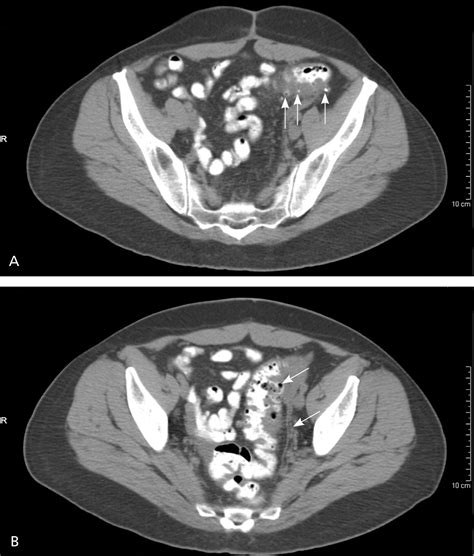

Diverticulitis is a painful condition that occurs when small pouches in the colon, known as diverticula, become inflamed or infected. When a patient presents with symptoms such as severe abdominal pain, fever, and changes in bowel habits, physicians must act quickly to make an accurate diagnosis. Among the various diagnostic tools available in modern medicine, a CT scan for diverticulitis is considered the gold standard. Its ability to provide detailed, cross-sectional images of the abdomen allows healthcare providers to confirm the presence of inflammation, assess the severity of the condition, and rule out other potential causes of abdominal distress.

Once the scan is completed, a radiologist will interpret the images and generate a report. If the scan confirms a diagnosis of diverticulitis, the radiologist will often grade the severity of the disease. This grading system is crucial for determining the appropriate course of treatment. The results of your CT scan for diverticulitis will likely focus on several key indicators:

• Wall Thickening: The degree to which the colon wall has thickened due to inflammation.

• Fat Stranding: A hazy appearance in the fat surrounding the colon, which is a classic sign of localized inflammation.

• Presence of Abscesses: Whether there are pockets of pus that may require drainage or specific antibiotic therapy.

• Free Air: A critical finding that may indicate a perforation, which is a medical emergency requiring immediate surgical consultation.